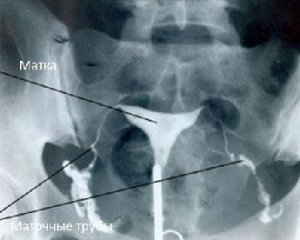

Гистеросальпингография

Проверка проходимости маточных труб с использованием гистеросальпингографии представляет собой рентгенологическое исследование, направленное на оценку состояния матки и маточных труб. Для выполнения данной процедуры необходимо ввести рентгенконтрастное вещество в полость матки. Это требует фиксации шейки матки специальными щипцами, что может вызывать определенные болезненные ощущения.

Еще одним недостатком данного метода является возможность попадания рентгенконтрастного вещества в брюшную полость, что может привести к образованию спаек. Кроме того, после исследования может возникнуть болевой синдром различной интенсивности, который обычно проходит самостоятельно в течение нескольких дней. Это связано с повышением давления в маточных трубах из-за наличия контраста. В связи с этими недостатками гистеросальпингография все чаще заменяется более современным ультразвуковым методом, который не имеет подобных проблем.

Тем не менее, у гистеросальпингографии есть одно важное преимущество – возможность получения рентгенологических снимков, что исключает субъективность в оценке результатов врачом. Это позволяет отслеживать динамику лечения, сравнивая снимки между собой. Однако из-за радиационной нагрузки не рекомендуется слишком частое повторение этой процедуры.

Интерпретация результатов исследования основывается на следующих принципах:

- наличие деформации полости матки и ее текущее состояние

- поступление контраста в брюшную полость

- визуализация маточных труб, при этом может наблюдаться их ампулообразное расширение без контраста в малом тазу, что указывает на полную непроходимость.